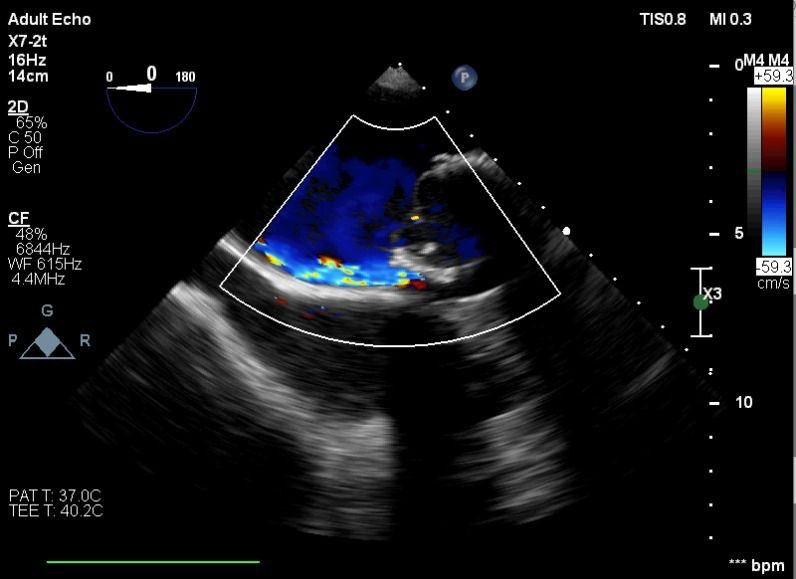

Balıkesir’de ilk nitelikli işlemlerin bir yenisi de Kardiyoloji Anabilim Dalı bünyesinde girişimsel kardiyoloji ile gerçekleştirilen paravalvüler kaçak kapatılması işlemi oldu. İşlem sırasında hastanın kalbi durdurulmadan ve göğüs kafesi kesilmeden, kasığından girilerek yapay kalp kapağındaki kaçak ameliyatsız kapatıldı.

Yapılan işlemi gerçekleştiren ekipte yer alan Prof. Dr. Halil Kısacık, Doç. Dr. Eyüp Avcı, Doç. Dr. Tarık Yıldırım ve Doç. Dr. Özgen Şafak konu hakkında açıklamalarda bulundu. Daha önce kalp kapakçığı değişim ameliyatı olan hastada takılan kapağın kenarından ayrılmasıyla kan kaçağı (paravalvuler leak) meydana geldiğini belirten öğretim üyeleri, Kardiyoloji Anabilim Dalına başvuran hastaya, Türkiye’de sayılı kalp merkezinde yapılan ve önemli düzeyde cerrahi deneyim gerektiren paravalvüler kaçak kapatılması işlemi uygulandığını dile getirdi. İşlemin sadece girişimsel kardiyologlar tarafından yapıldığının altını çizen öğretim üyeleri, işlem sırasında hastanın kalbi durdurulmadan ve göğüs kafesi kesilmeden, kasığından girilerek yapay kalp kapağındaki kaçağın ameliyatsız kapatıldığını söyledi.